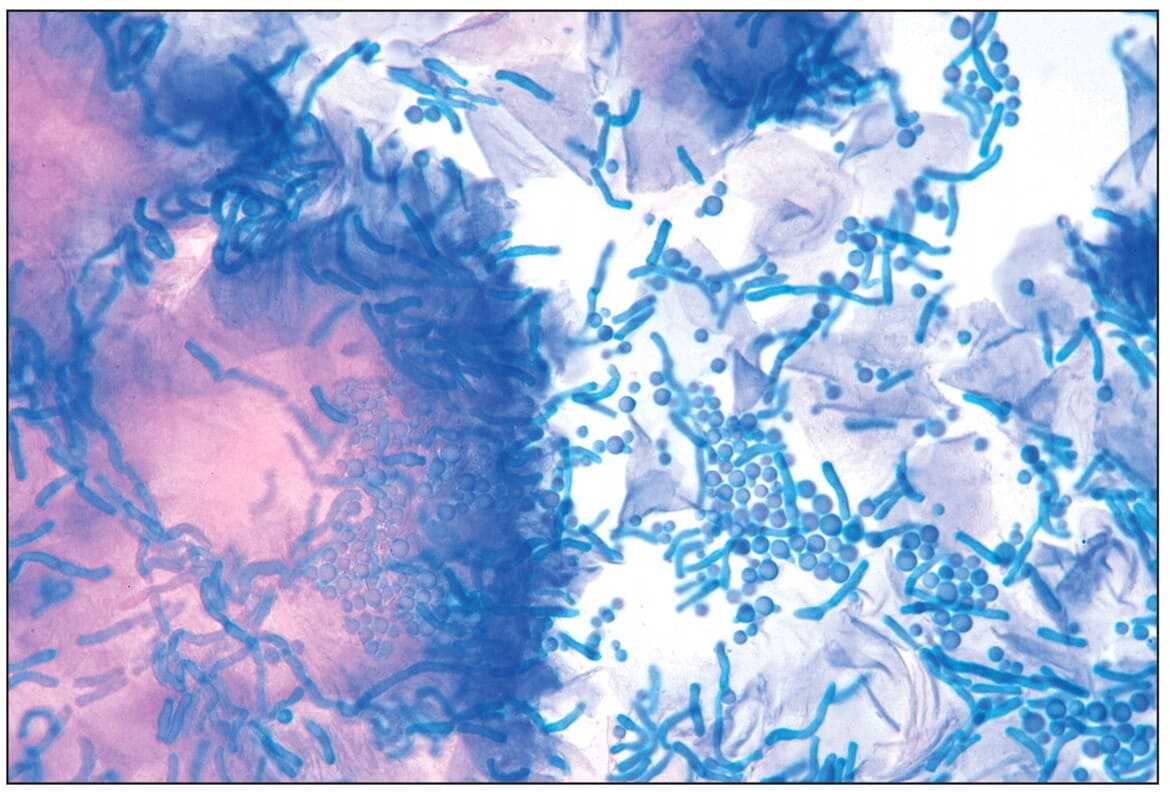

- избыточное размножение грибка Malassezia Furfur и Pityrosporum ovale;

На волосистой части головы у всех людей обитает дрожжевой грибок рода Malassezia. При определенных условиях он начинает активно размножаться, провоцируя развитие себореи и вызывая активное шелушение кожи головы, которое, в свою очередь, вызывает появление неприятных хлопьев перхоти.